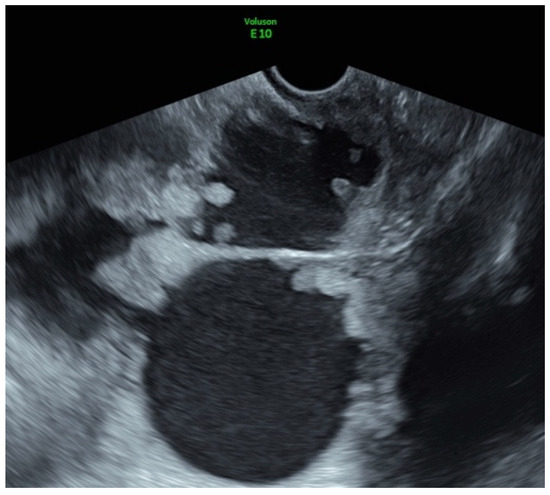

| Largest diameter of the lesion (mm): median (min-max) | 51 (8–280) |

| Type of the tumor (N, %) | |

| Solid | 34 (81%) |

| Multilocular-solid | 8 (19 %) |

| Tumor margins (N, %) | |

| Irregular | 36 (85.7%) |

| Regular | 6 (14.3%) |

| Color score (N, %) | |

| 2 | 10 (23.8%) |

| 3 | 29 (69%) |

| 4 | 3 (7.1%) |

| Ascites (N, %) | 12 (28.6%) |